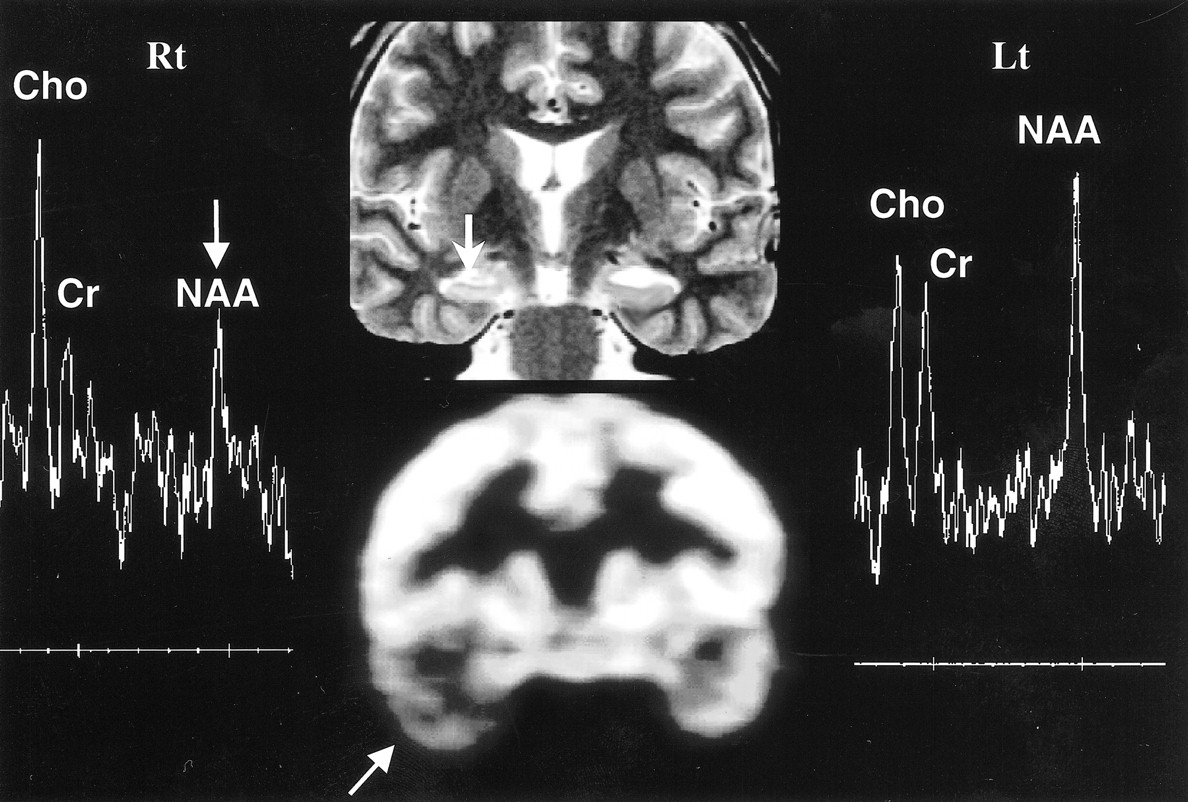

Bilateral abnormality on MRS in left hippocampal sclerosis. Oblique coronal T2-weighted MR image (top row, middle) shows left hippocampal sclerosis with increased signal intensity (arrow), in concordance with PET scan (bottom row, middle), which shows decreased metabolism (arrow) in left temporal lobe. The MR spectra (Rt and Lt) show bilateral abnormalities (arrows), decreased NAA/Cho ratios bilaterally, and decreased NAA/Cr ratio on right side